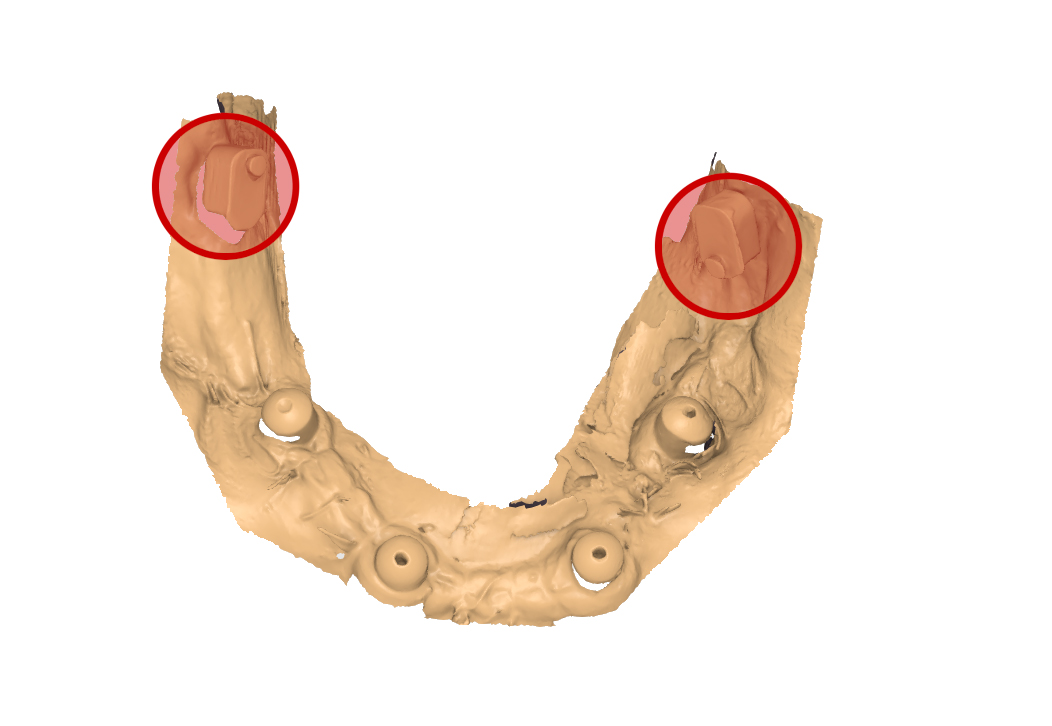

file .stl dell’impronta inferiore

Fig. 7. (b) File .stl dell’impronta inferiore rilevata con dima di scansione universale e scanbody implantari, in evidenza gli ScanSke.

file .stl dell’impronta inferiore delle mucose

Fig. 7. (c) File .stl dell’impronta inferiore delle mucose, in evidenza gli ScanSke.